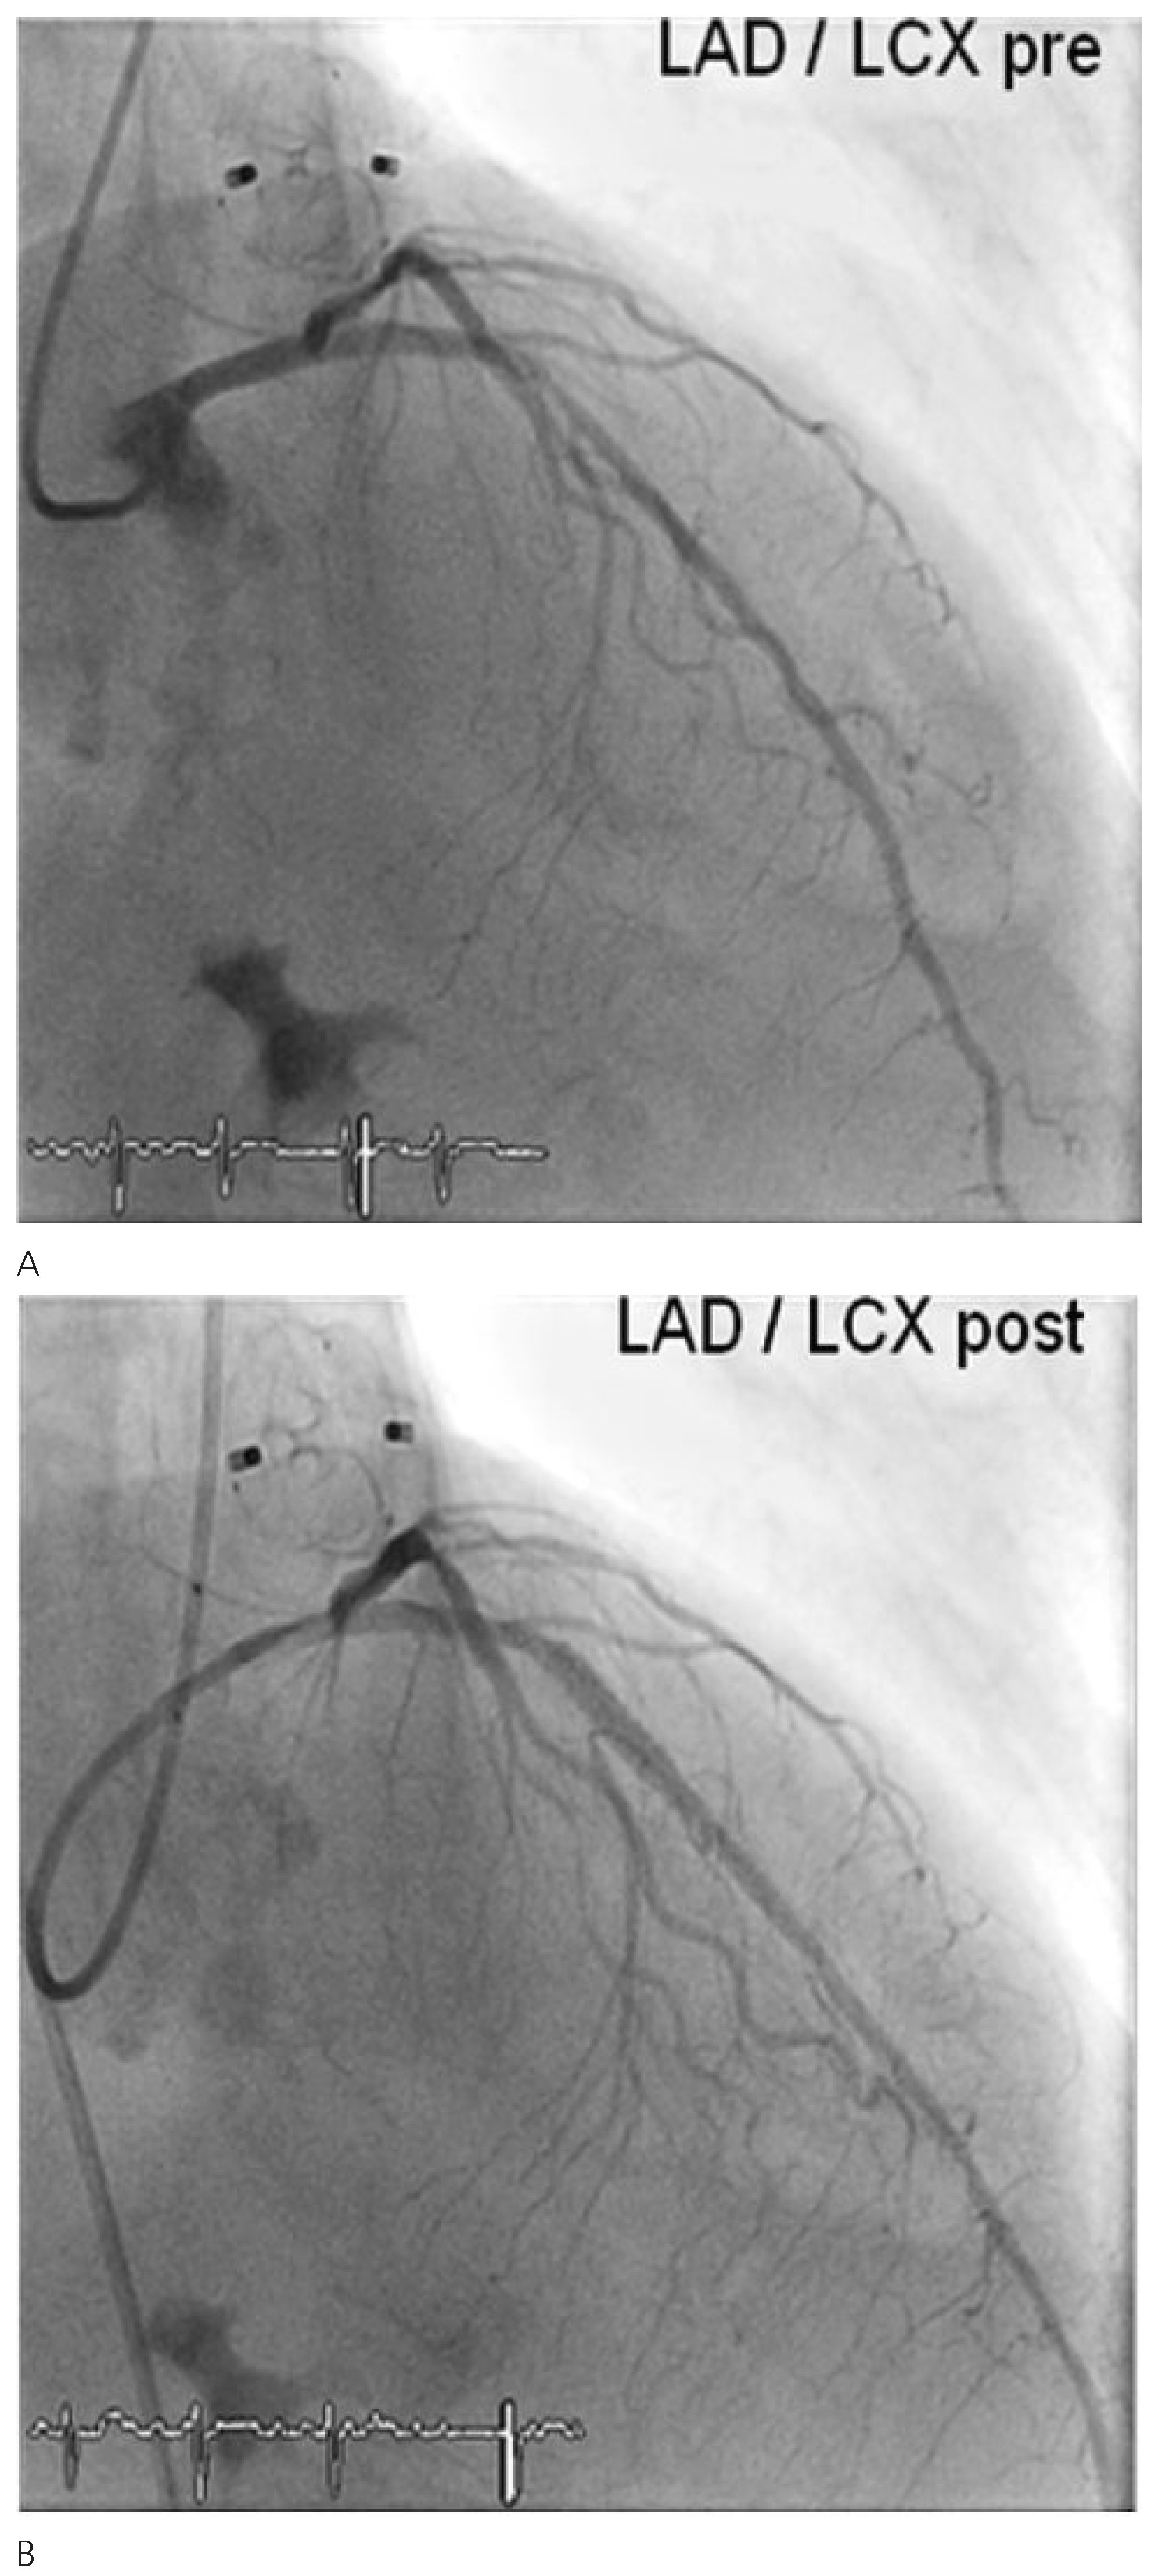

Figure 2). Thereafter, coronary angiography was performed which showed significant stenosis of the mid left anterior descending coronary artery (LAD) and the proximal left circumflex coronary artery (LCX). Following successful treatment with two everolimus-eluting stents, respectively (

Figure 3), angiography of the aorta and iliac artery was performed to measure the aortic valvar annulus and assess the peripheral access site. The patient qualified for implantation of a Medtronic CoreValve bioprosthesis and a 18 French sheath was introduced in the right femoral artery, as well as a temporary transvenous pacemaker through a right jugular access. After balloon dilatation of the degenerative aortic valve with a Nucleus balloon 25 × 40 mm under rapid pacing, the self-expandable bioprosthesis was deployed under fluoroscopic guidance (